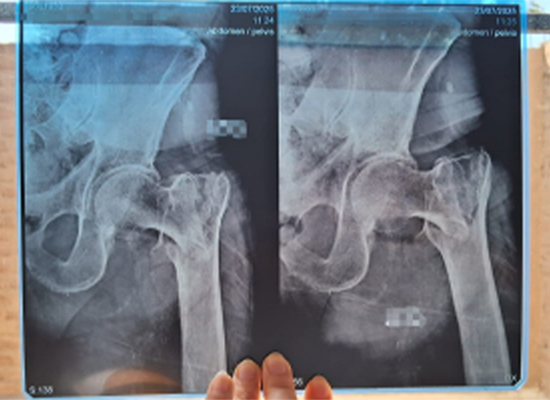

Radiographic imaging confirmed a displaced left intertrochanteric fracture, requiring timely surgical intervention to restore stability and mobility.

Preoperative X-ray showing displaced left intertrochanteric fracture in elderly patient, Lima Peru

The patient, Ms. Ana Marisol Vásquez, an 82-year-old female with a medical history of arterial hypertension, presented to the hospital after a domestic fall. She reported severe left hip pain and complete inability to bear weight.

Visible deformity around the left hip

Markedly limited range of motion

Tenderness at the intertrochanteric region

Abnormal lower limb alignment